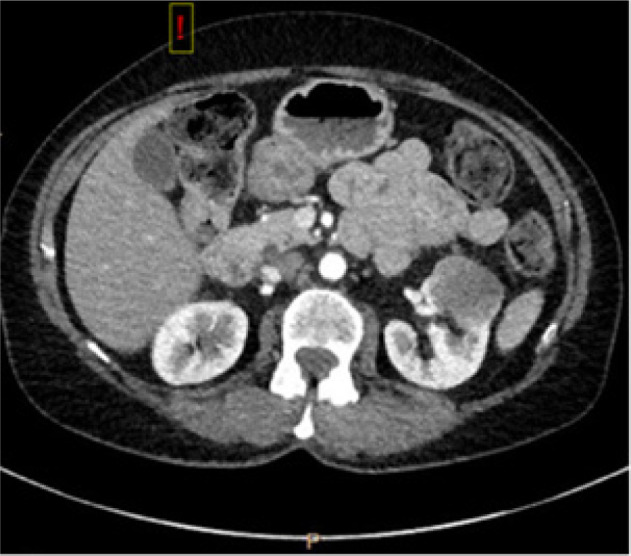

Adenoid cystic carcinoma (ACC) is a rare tumor, accounting for 1% of all head and neck cancers, with an aggressive nature characterized by local recurrence, delayed metastasis, and survival of less than 50% at 10 years. This is a case of biopsy-proven ACC to the kidney, 1 of 29 known occurrences, managed by metastasectomy by robotic-assisted nephrectomy, with plans for resection of lung metastasis. Thirteen years after diagnosis of sinonasal ACC treated with resection, the patient presented with shortness of breath. This prompted a CT scan of the chest, which led to the incidental finding of left renal mass and pulmonary lesion. Literature suggests improved disease-specific survival in locoregional recurrence treated with surgery versus radiation; in patients with metastasis to the lung, metastasectomy offers greater survival benefit than supportive therapy. But, this is not significantly better than chemotherapy or radiation alone. While the optimal therapeutic approach remains to be identified in distant metastatic ACC, metastasectomy remains a viable option for patients who have potentially completely resectable metastatic tumors, appropriate performance status, and adequate affected-organ function. Preoperative counseling should include discussion on partial nephrectomy with prioritization of nephron-sparing but potential for increased perioperative risk versus radical nephrectomy to ensure negative margins and expedite timeline to systemic therapy.

Abstract Image